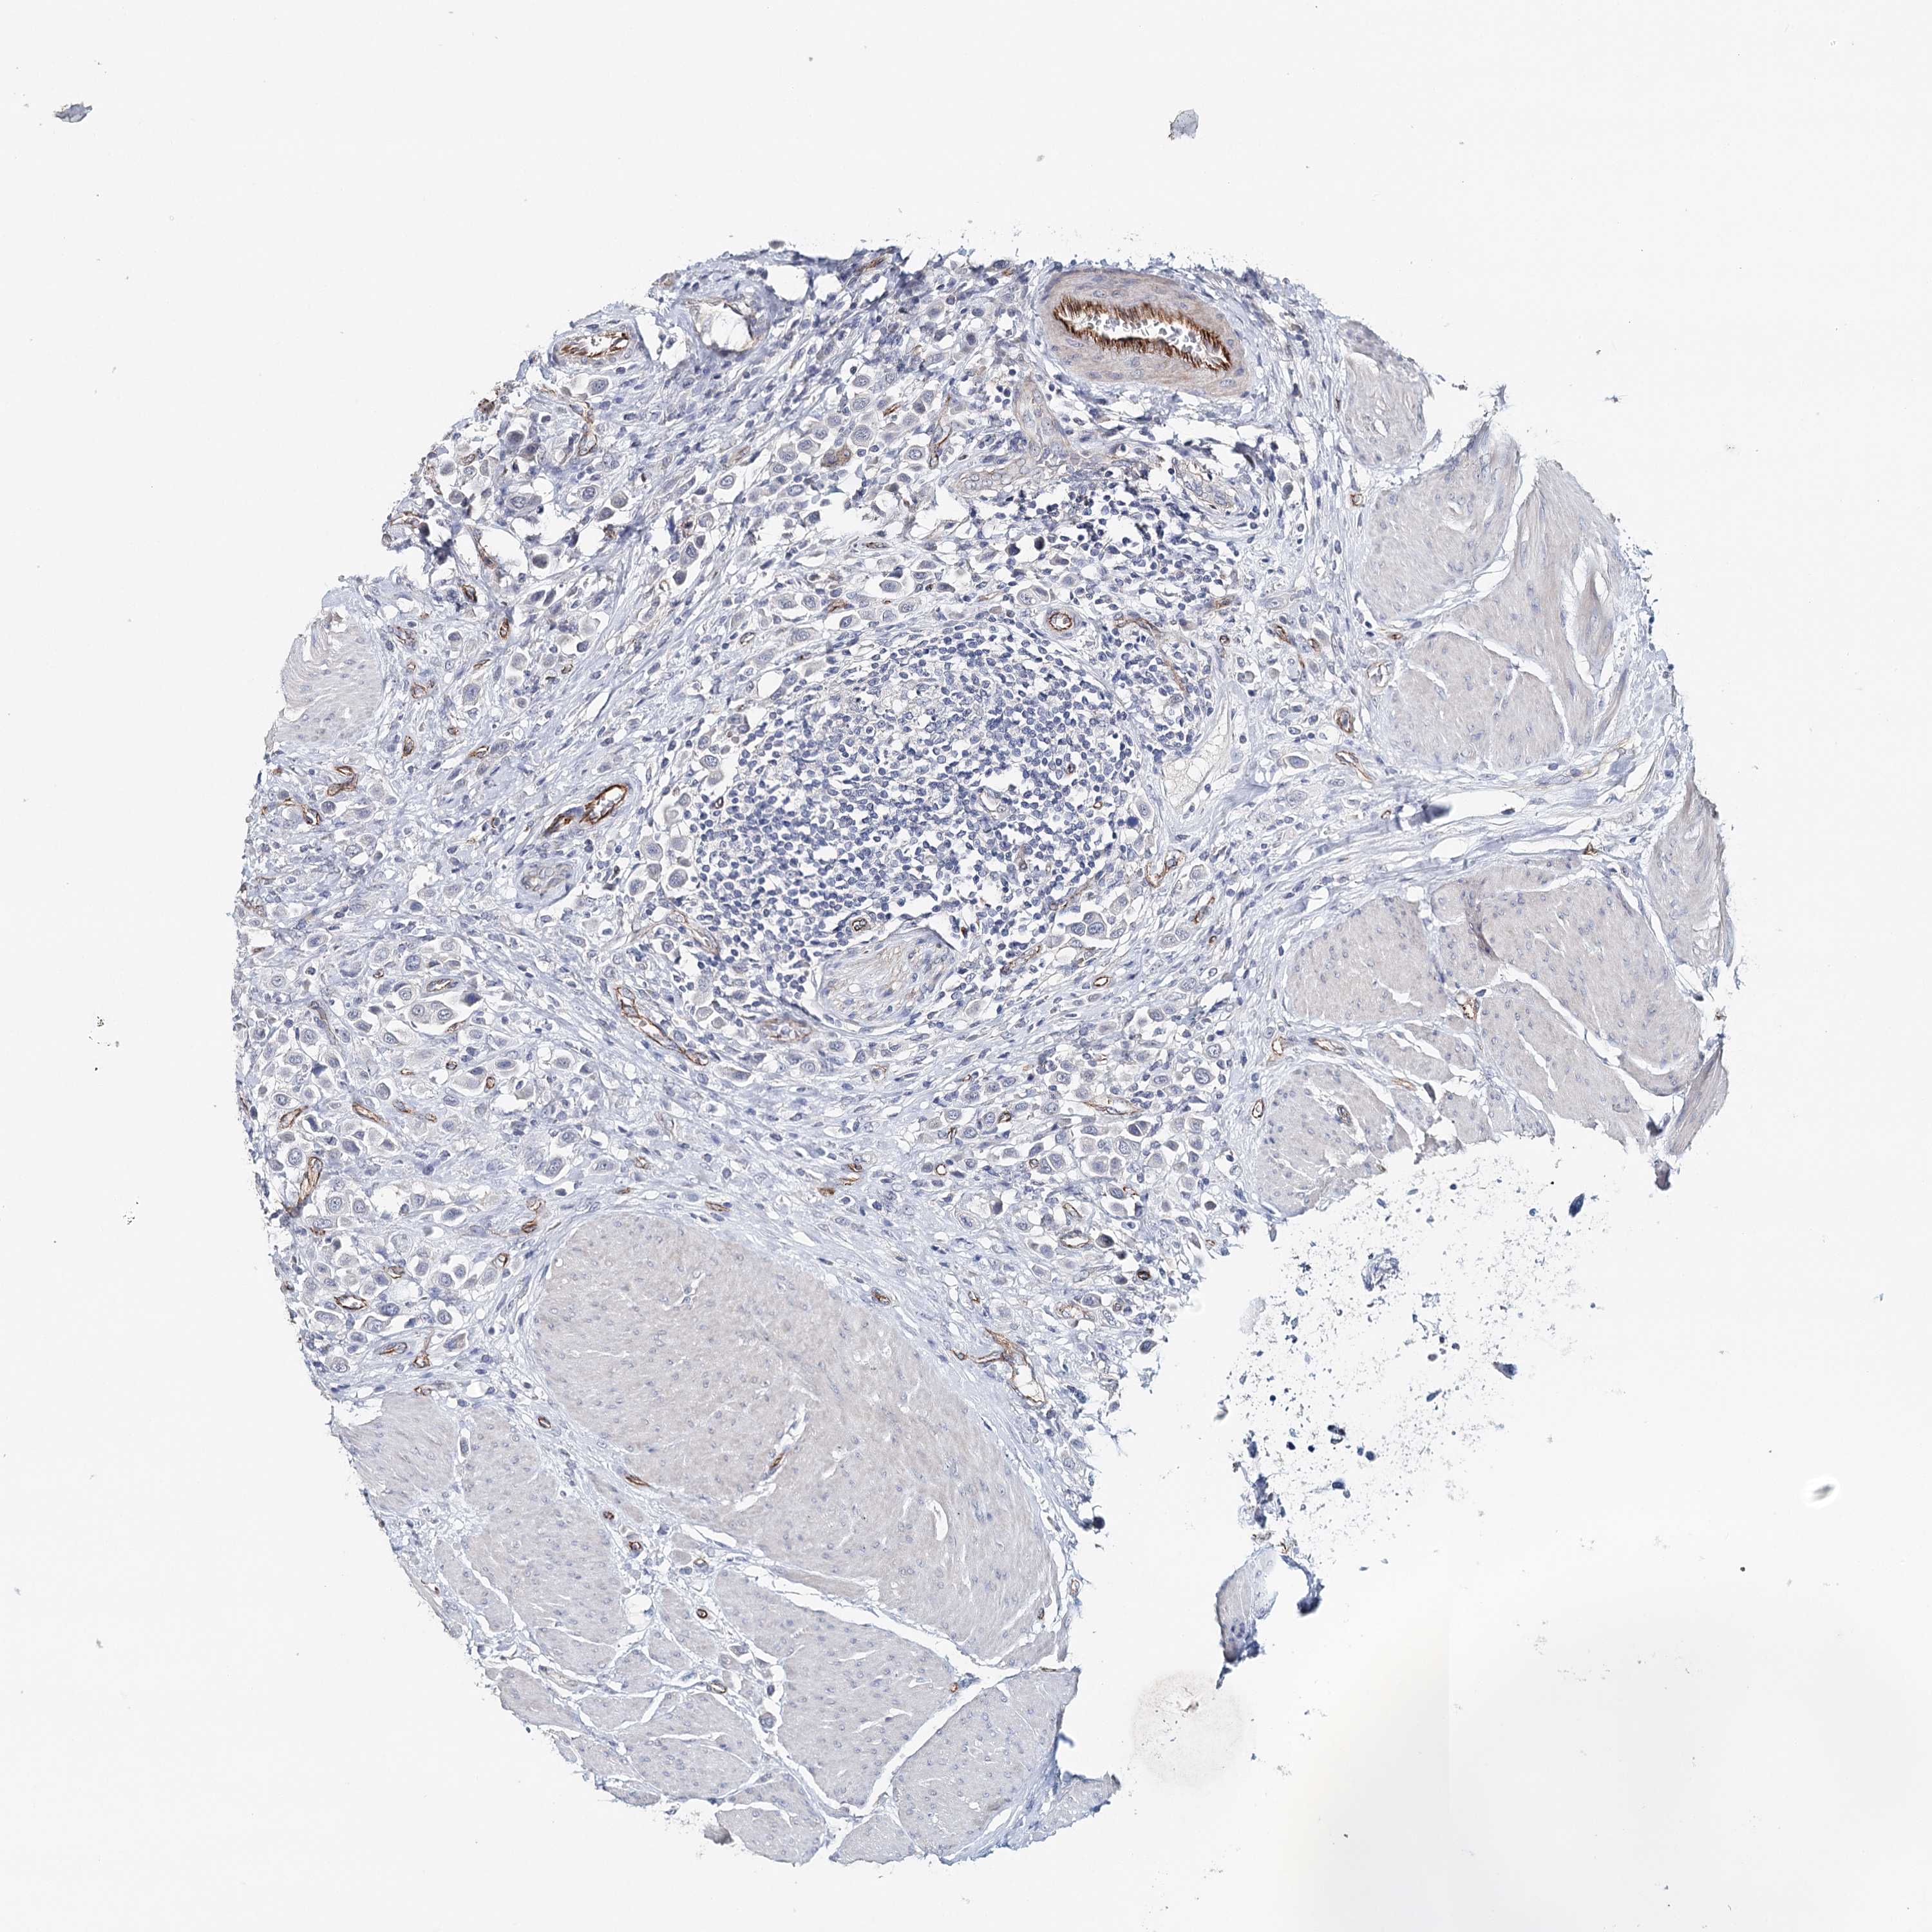

UROTHELIAL CANCER - Protein expressioni

A mouse-over function shows sample information and annotation data. Click on an image to view it in a full screen mode. Samples can be filtered based on level of antibody staining by selecting one or several of the following categories: high, medium, low and not detected. The assay and annotation is described here.

Note that samples used for immunohistochemistry by the Human Protein Atlas do not correspond to samples in the TCGA dataset.

Antibody stainingi

Antibody staining in the annotated cell types in the current human tissue is reported as not detected, low, medium, or high, based on conventional immunohistochemistry profiling in selected tissues. This score is based on the combination of the staining intensity and fraction of stained cells.

Each image is clickable and will lead to virtual microscopy that enables deeper exploration of all samples and also displays staining intensity scores, fraction scores and subcellular localization as well as patient and tissue information for each sample.

Urothelial carcinoma, High grade

Urothelial carcinoma, Low grade

Urothelial carcinoma, NOS